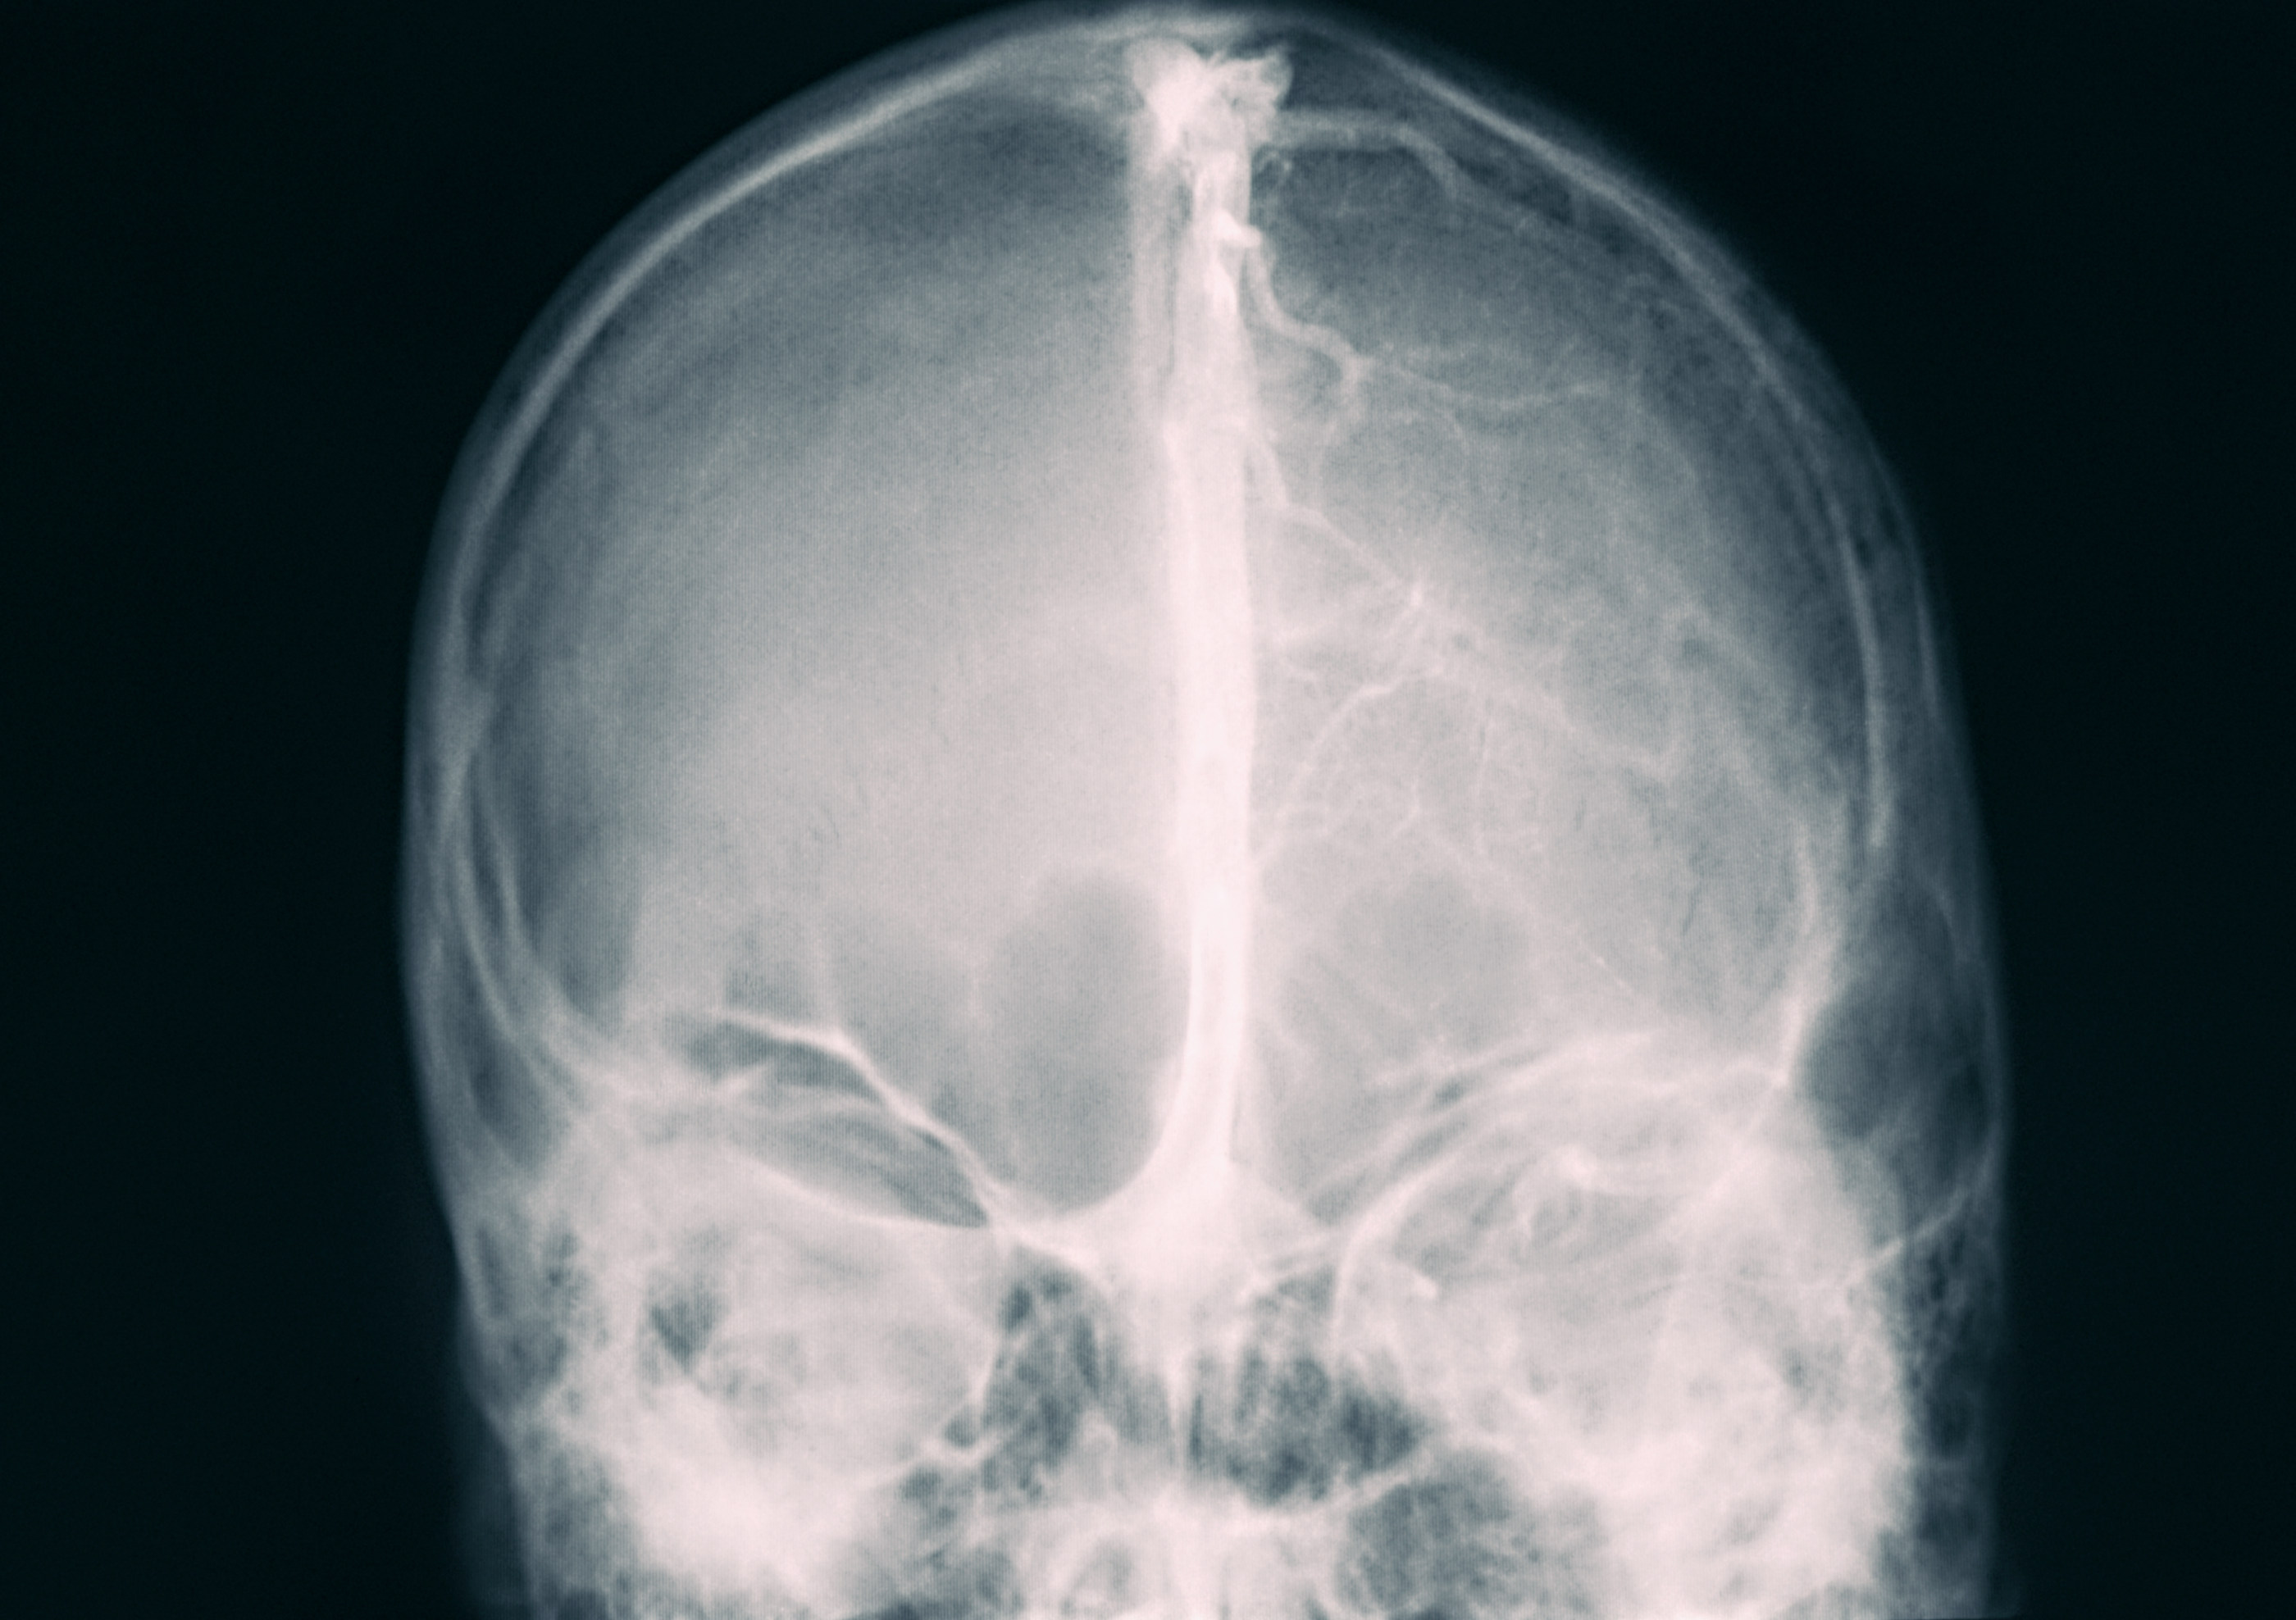

Dr. Mignot explains that hypocretins (orexins) are molecules

located in a sub-region of the hypothalamus brain structure which are especially important for the regulation of appetite. Two teams of researchers discovered hypocretins around the same time; the second research group calls them orexins. Mignot points out in his article that one scientist has suggested they now change the name to “narcoleptins”!

Right now, the only way to test for missing narcoleptins is to perform a painful procedure called a lumbar puncture (spinal tap). Researchers hope to develop an easier method for testing, such as measuring narcoleptin levels in blood.